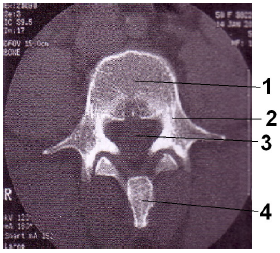

Assinale a alternativa que representa, em ordem crescente, as estruturas assinaladas na imagem tomográfica anteriormente apresentada.

1- corpo vertebral, 2- processo transverso, 3- forame transversário, 4 - processo espinhoso.

1– disco vertebral, 2- pedículo, 3- forame vertebral, 4 processo transverso.

1- corpo vertebral, 2- pedículo, 3- forame vertebral, 4 processo espinhoso.

1- disco vertebral, 2- processo espinhoso, 3- forame transversário, 4- processo transverso.